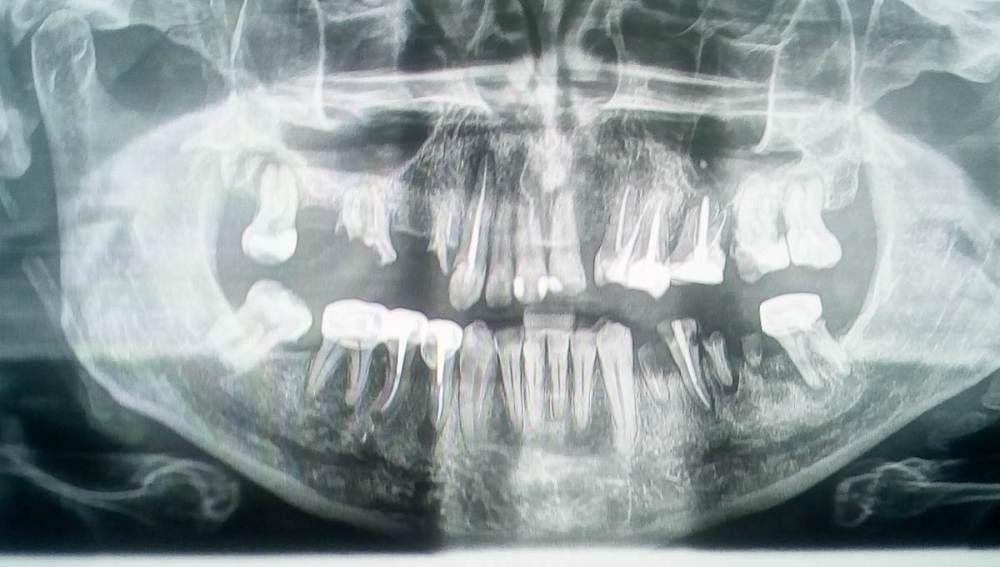

JohnREO Опубликовано 14 ноября, 2021 Поделиться Опубликовано 14 ноября, 2021 Здравствуйте, мне предлагают удалять 5 рабочих зубов, поскольку там киста и нет местами костной ткани. Посоветуйте пожалуйста хорошего специалиста по зубосохраняющим операциям, хочу узнать - есть ли возможность сохранить эти зубы? Ссылка на комментарий

red_butler Опубликовано 14 ноября, 2021 Поделиться Опубликовано 14 ноября, 2021 1.8 1.6 1.4 2.8 3.6 3.4 4.8 удалять. Остальные повторное лечение корневых каналов, но 2.6 прогноз плохой. Зубо сохраняющие операции не нужны. 3 Ссылка на комментарий

Bier Опубликовано 6 декабря, 2021 Поделиться Опубликовано 6 декабря, 2021 наверху тут тотальчик просится уже, на имплантатах. Ссылка на комментарий